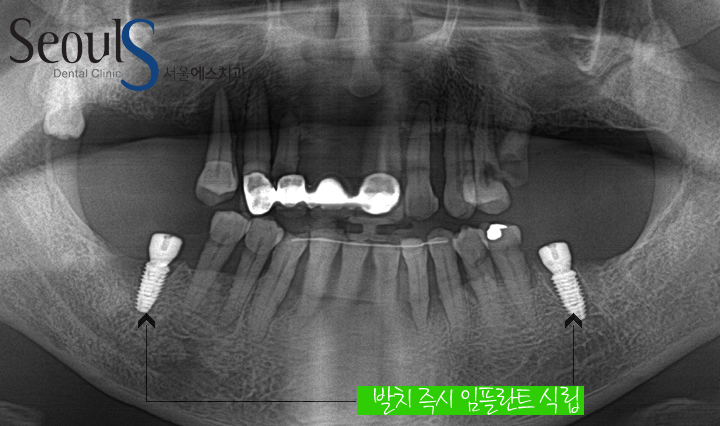

파노라마 X-ray 사진입니다

윗니는 잇몸뼈가 녹았서 치아를 잡아주지 못하는 상태이고

치아 뿌리에 염증이 진행되고 있습니다

아랫니는 맨 끝 어금니가 위로 올라 온 모습입니다

어금니가 위로 올라온 이유는

마주보는 치아가 빠진 후 오랜 시간 방치했기 때문입니다

그리고 올라온 치아를 보시면

잇몸 뼈 파괴로 치아를 잡아주지 못해 안타깝지만 살릴 수 없는 상태였습니다

살릴수 없는 아랫니는 발치 즉시 임플란트를 식립했고

바로 임시치아를 결합했습니다

윗니는 발치후 잇몸뼈와 잇몸이 회복 되길 기다린 후 임플란트를 식립 할 예정입니다